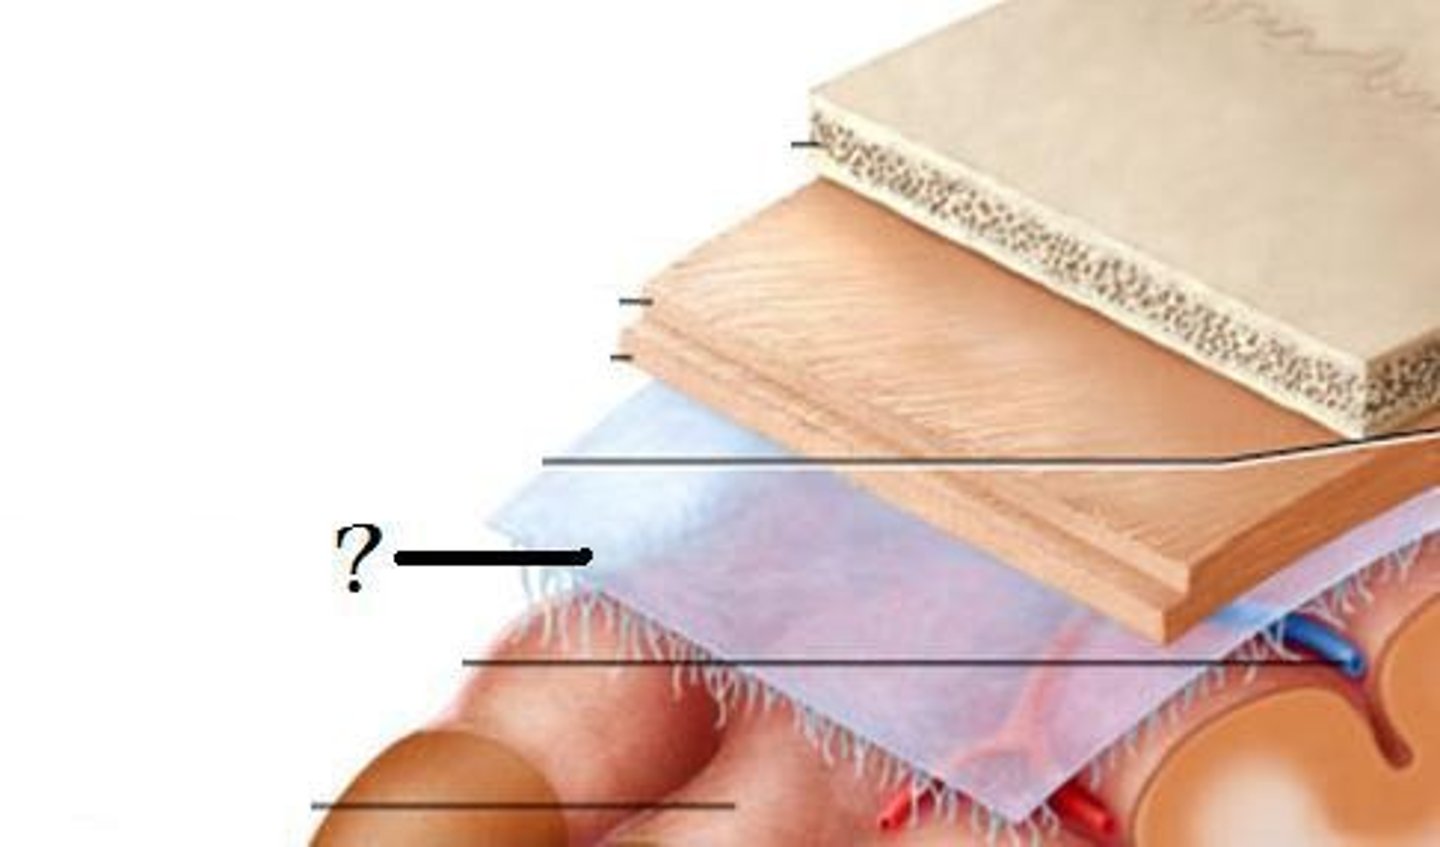

3 layers make up the meninges

dura mater, arachnoid mater, pia mater

dura mater

outer periosteal layer & inner meninges layer

periosteal and meningeal

two layers of dura mater

arachnoid

middle layer of meninges; weblike appearance that attaches it to deepest layer

arachnoid trabeculae

subdural space

space between dura mater and arachnoid mater

subarachnoid space

skin of scalp

arachnoid mater

pia mater

the delicate innermost membrane enveloping the brain and spinal cord.

leptomeninges

The pia mater and arachnoid together